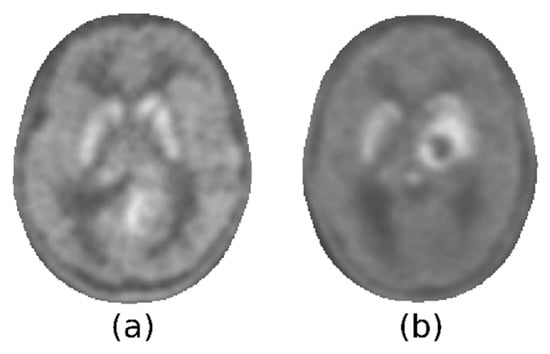

Figure 3.

Axial section showing a tumor that does not affect striatum (a) and one that has reached it (b).

The maximum intensities within the lesions, in Pn and Ps, are conceptually analogous to the TN and TS derived with the manual procedure (Equation (1)). If we denote by Mc all the voxels of the brain except Mn and Ms, the mask obtained contains both the striatum within the lesioned hemisphere and the glioma. To compare the results of the two procedures, it was necessary to identify a value corresponding to the local maximum intensity of the lesion, and this search was limited to Mc. There are two criticalities in the definition of this value. The first is related to the presence of the striatum in the volume Mc. This subcortical structure presents a tracer uptake that could be comparable to that of the glioma. Consequently, it is possible for a minimum of two hyperintense areas to be observable, one of which may remain unaltered by the tumor and where the highest degree of uptake may be localized. The key point here is that it was not possible to discriminate the increased uptake of the healthy striatum from the increased uptake of lesions. It was also impossible, relying only on [18F]F-DOPA PET, to determine whether the infiltration of the striata by the glioma had clearly occurred. Figure 3 illustrates two examples of this heterogeneity: the tumor could present with less, more, or as much activity as the striatum, which could be spared by the tumor or not.